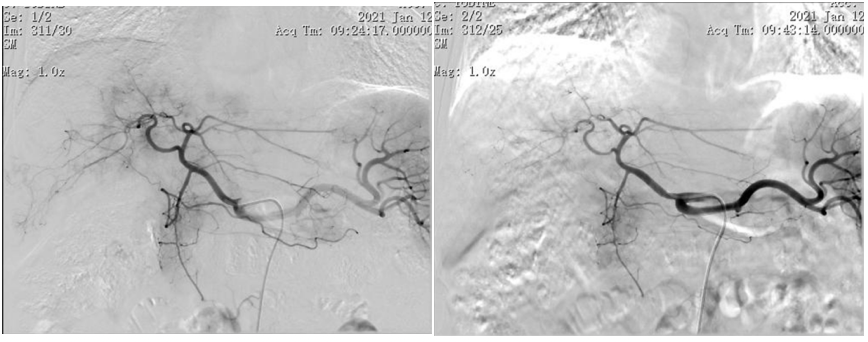

2020年11月27日行第1次经导管肝动脉化疗栓塞(TACE)治疗(图2)。

图2.2020年11月27日第一次TACE

2021年1月12日行第2次TACE治疗(图4)。后针对左侧肾上腺行局部放射治疗。2021年1月18日即第2次TACE术后6天AFP为165.8ng/ml。

图4.2021年1月12日第2次TACE治疗